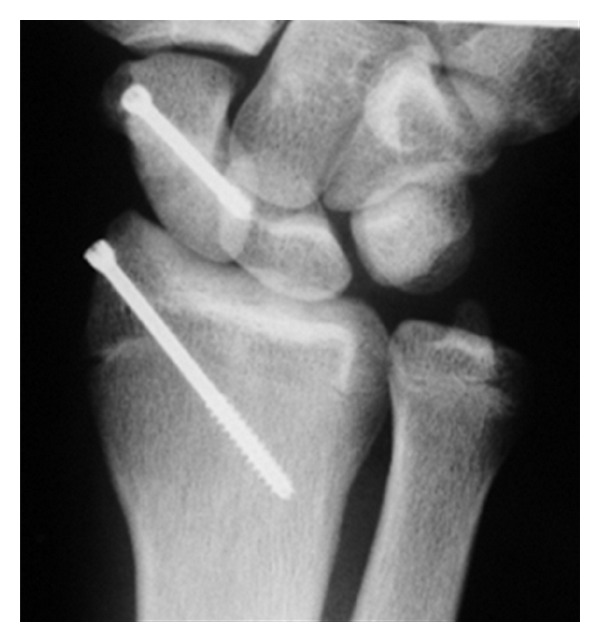

We decided on operative treatment with scaphoid percutaneous fixation and radial styloid process in situ fixation (Figure 3).

Figure 3.

Plain PA radiograph shows the percutaneous fixation and radial styloid process in situ fixation 8 weeks after operation.